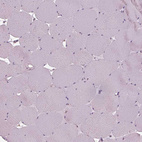

Immunohistochemistry analysis in human rectum and skeletal muscle tissues using HPA073666 antibody. Corresponding SRI RNA-seq data are presented for the same tissues.